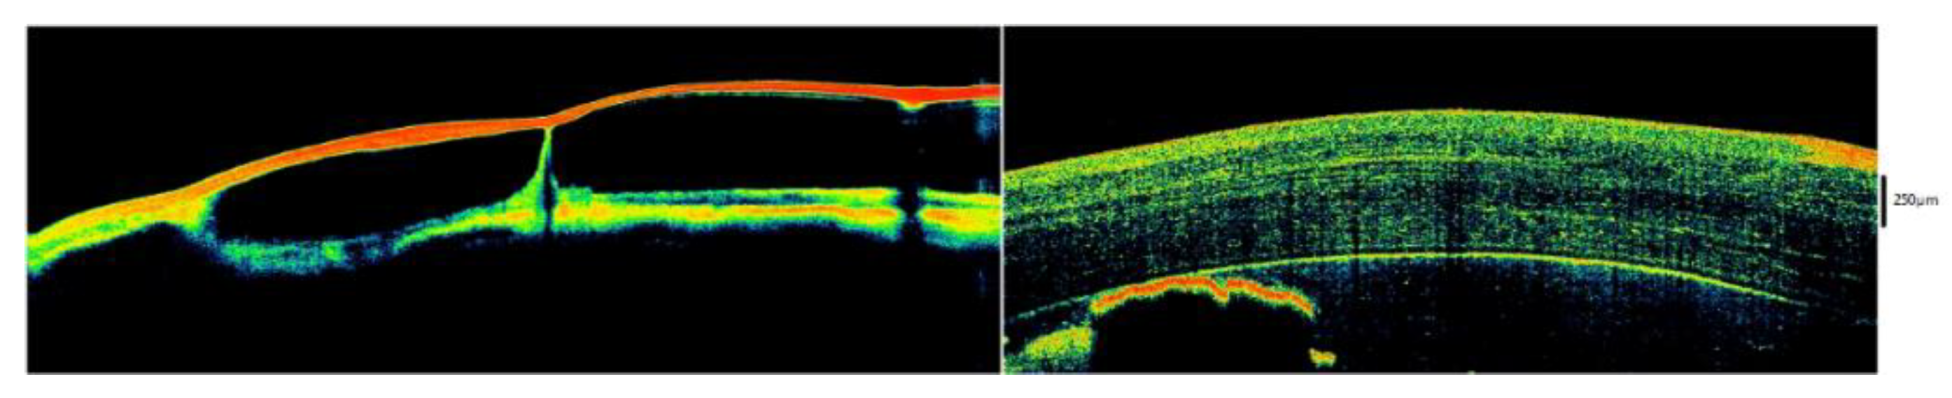

5. Tear Meniscus